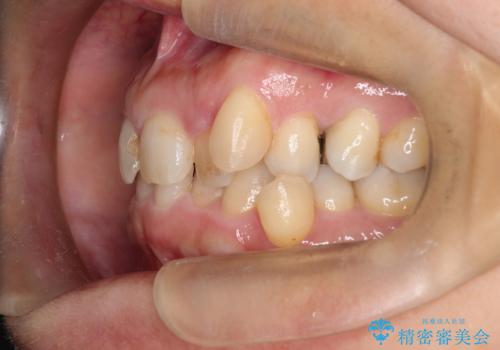

【インビザライン】重度叢生をなおしたい

- 全体的に歯並びをなおしたいことを主訴に来院されました。

上顎前歯が舌側傾斜していたため少し拡大を行いながら非抜歯で治療を行っています。

マウスピースをしっかり使用していただいたので、きれいな歯並びになりました。